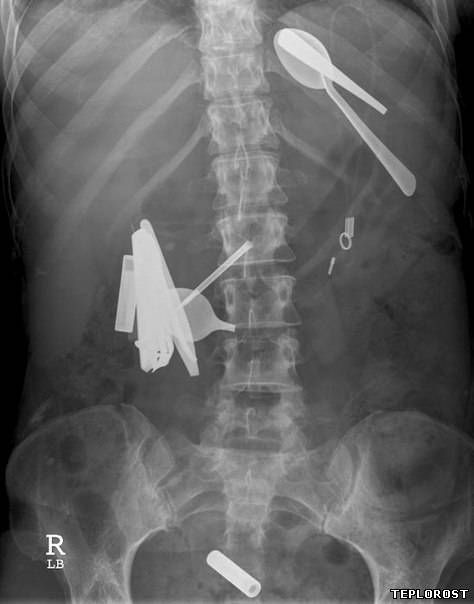

Столовые приборы и зубная щетка в желудке пациента.